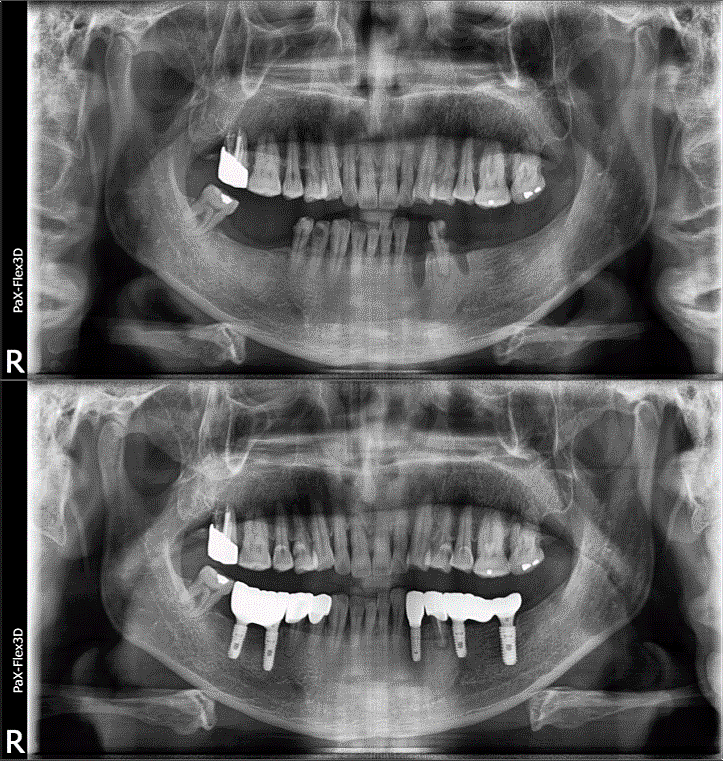

| 보험 임플란트 치료 사례 |

69세 남성

(전) 2021-11-05, (후) 2022-08-26

상기 환자분 오른쪽 아래 # 46, 47 어금니 2개 보험임플란트와 나머지 치아도 함께 치료받으신 사례입니다.

보험임플란트는 잇몸뼈가 충분하여 별도의 뼈이식술 없이 진행하였고요.

그 외 # 33 치아 임플란트를 식립하고, 그 옆에 # 34 치아는 크라운 씌워서 마무리했습니다.

그리고 # 35, 37에 임플란트 식립하고, 가운데 # 36 자리는 임플란트 폰틱(아래 사진 참고)이라 하여 브릿지와 같이 중간을 연결하는 가짜 치아로 시술해 드렸습니다.

전후 사진을 보시면 상당 부분 비어있던 치아들이 메워져 음식 섭취는 물론이고 심미적인 측면으로도 훨씬 개선된 모습을 확인하실 수 있습니다. ^^